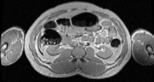

Visible Human male: Sectio transversalis 1633

CT

NMR

Pd                          / T2 \                         T1